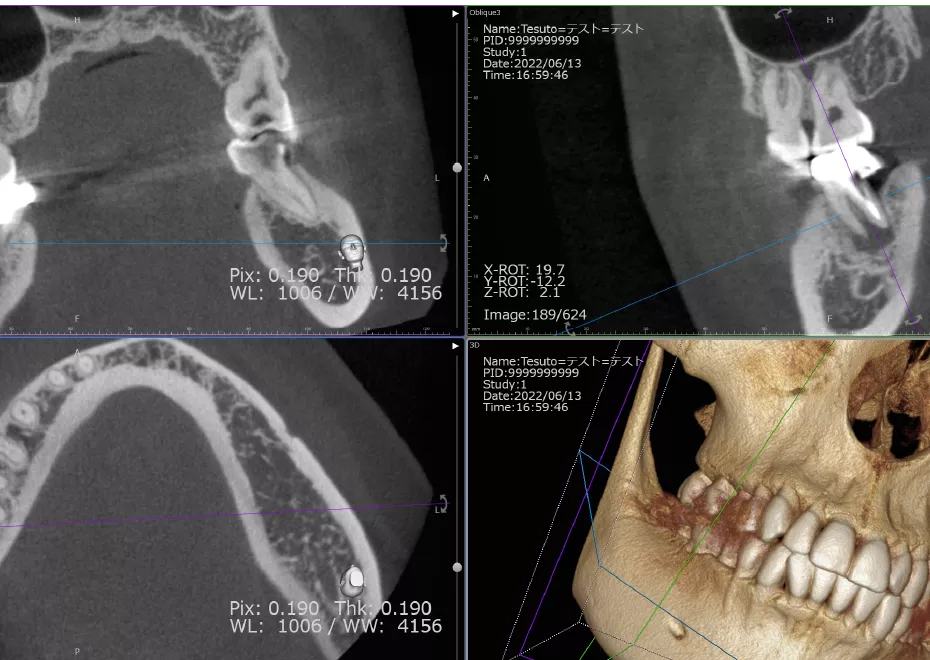

お口の中のお写真やレントゲン撮影、

CT撮影、模型印象などを採らせて頂きます。